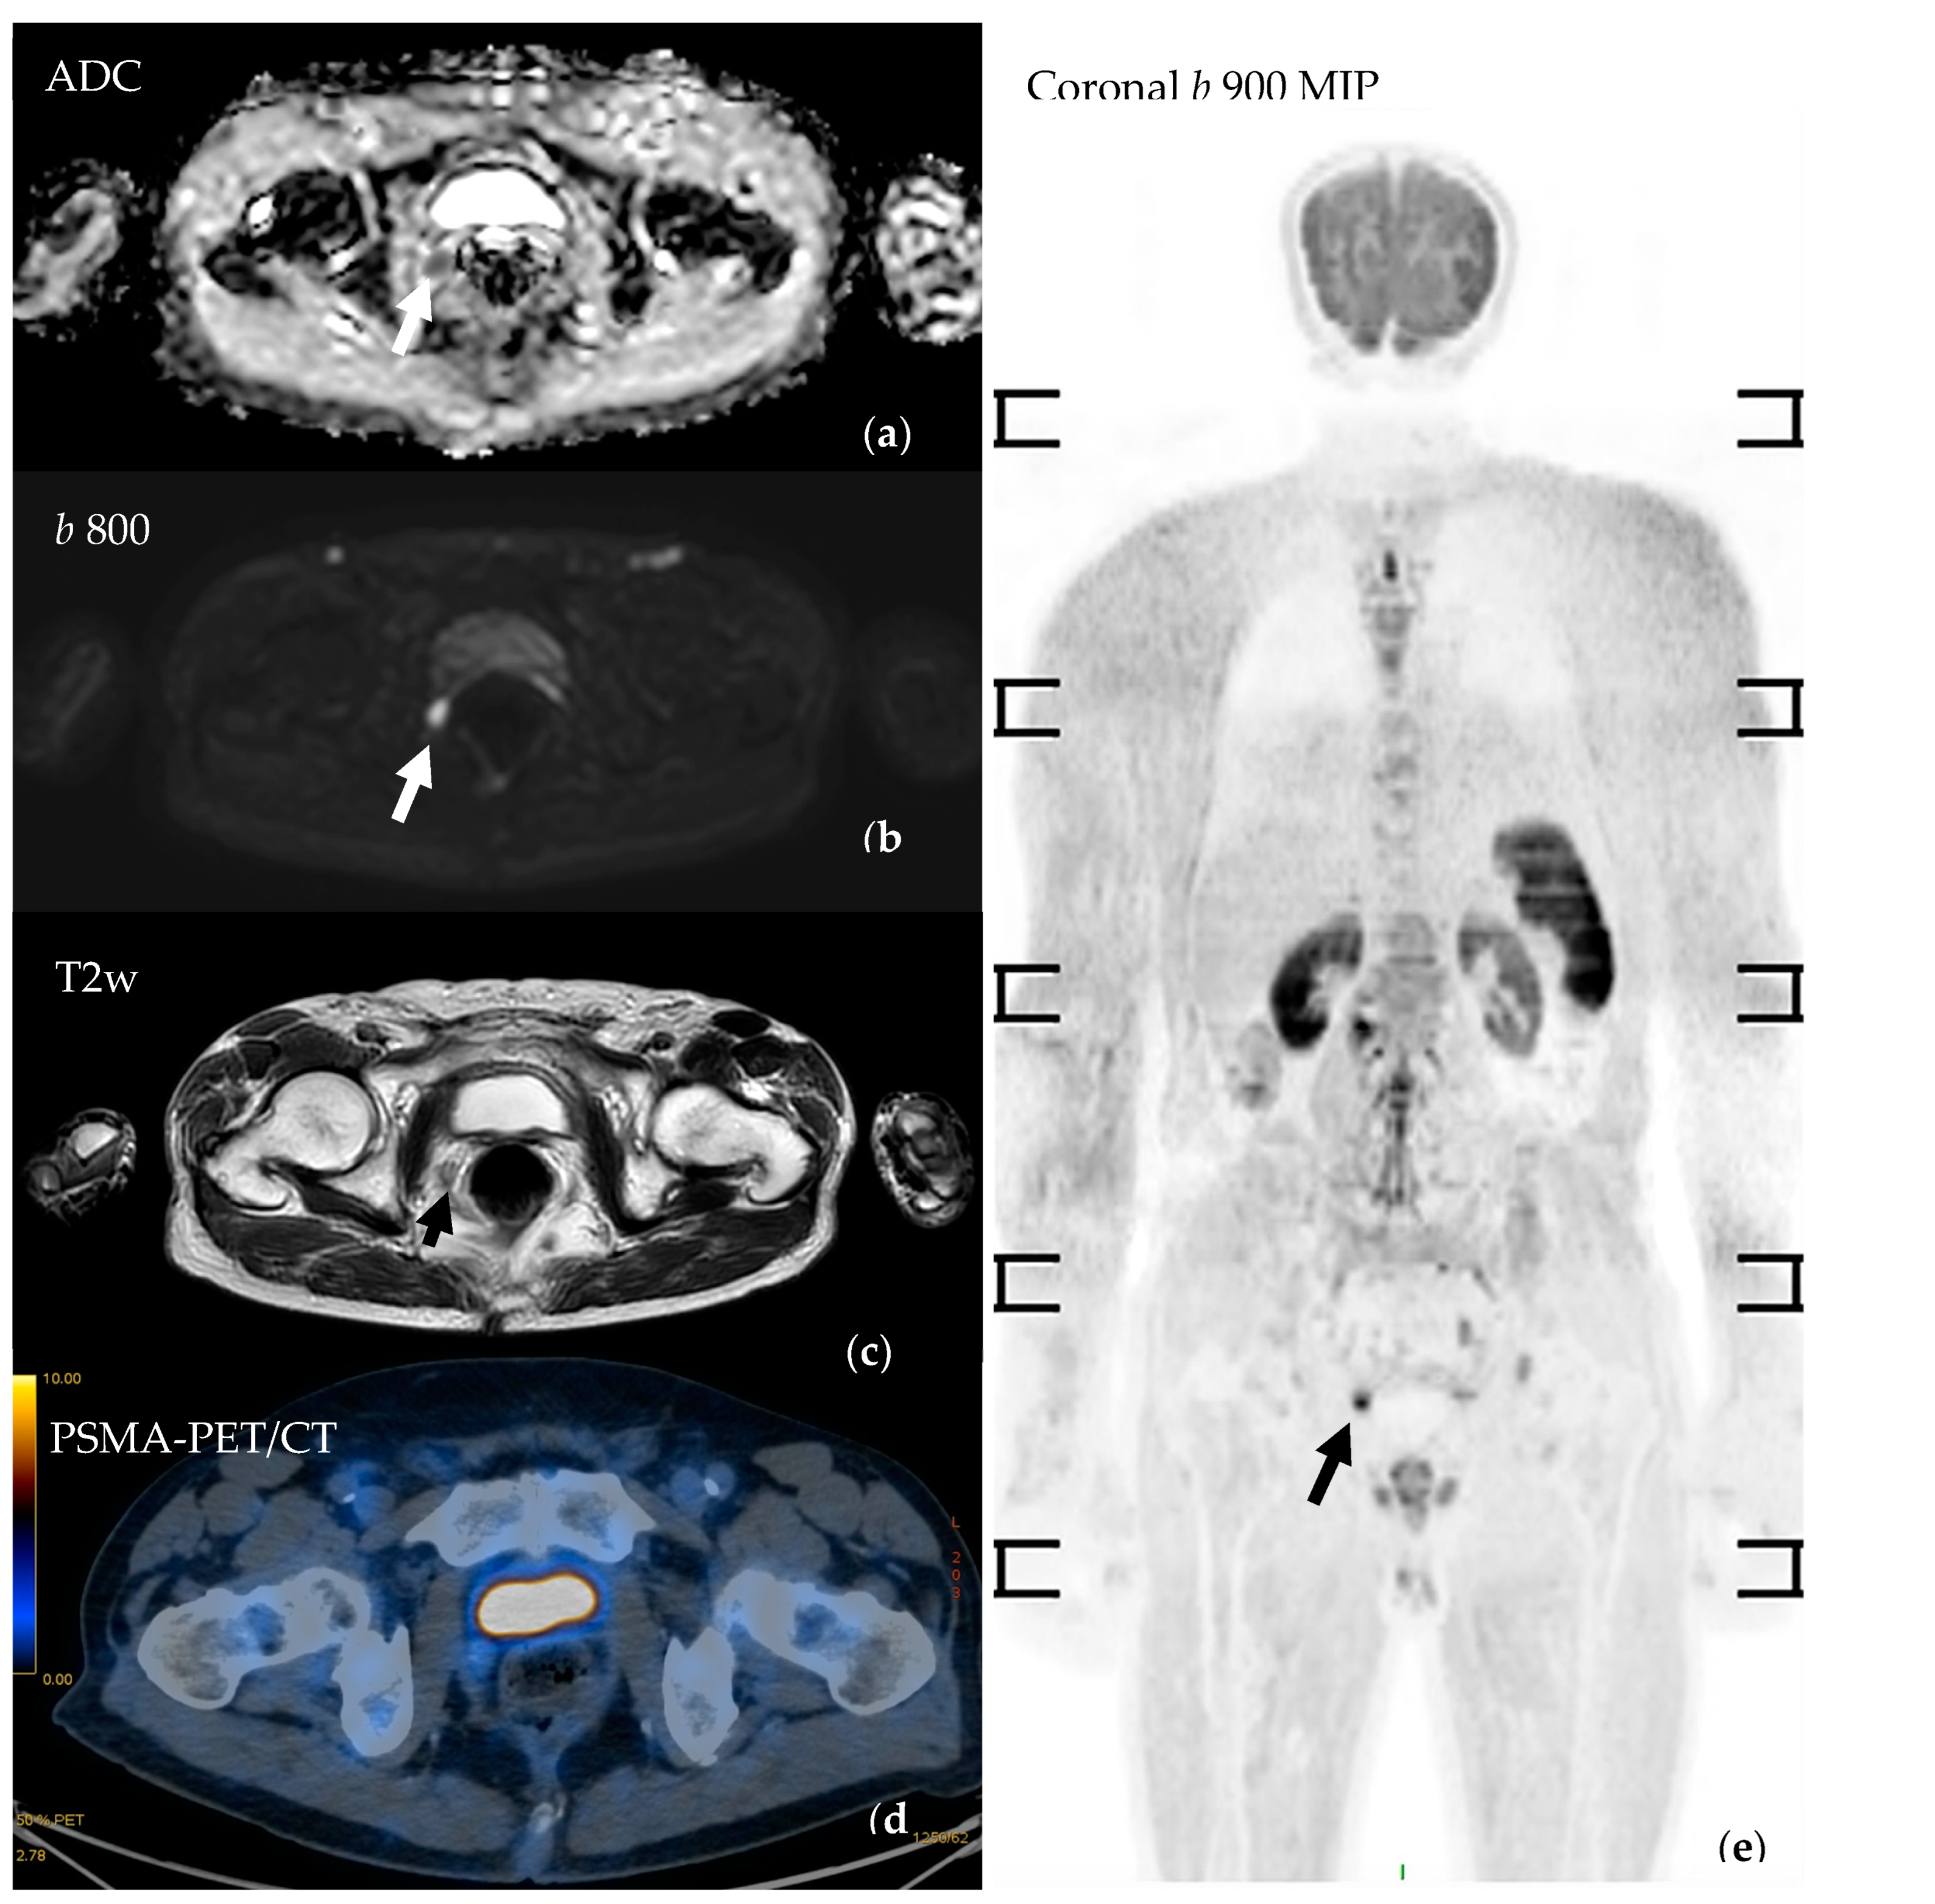

3.4.2. Assessment of Nodal Disease

3.4.4. Assessing Local Disease and Biochemical Recurrence

- Van Damme, J.; Tombal, B.; Collette, L.; Van Nieuwenhove, S.; Pasoglou, V.; Gérard, T.; Jamar, F.; Lhommel, R.; Lecouvet, F.E. Comparison of Ga-Prostate Specific Membrane Antigen (PSMA) Positron Emission Tomography Computed Tomography (PET-CT) and Whole-Body Magnetic Resonance Imaging (WB-MRI) with Diffusion Sequences (DWI) in the Staging of Advanced Prostate Cancer. Cancers 2021, 13, 5286. [Google Scholar] [CrossRef] [PubMed]